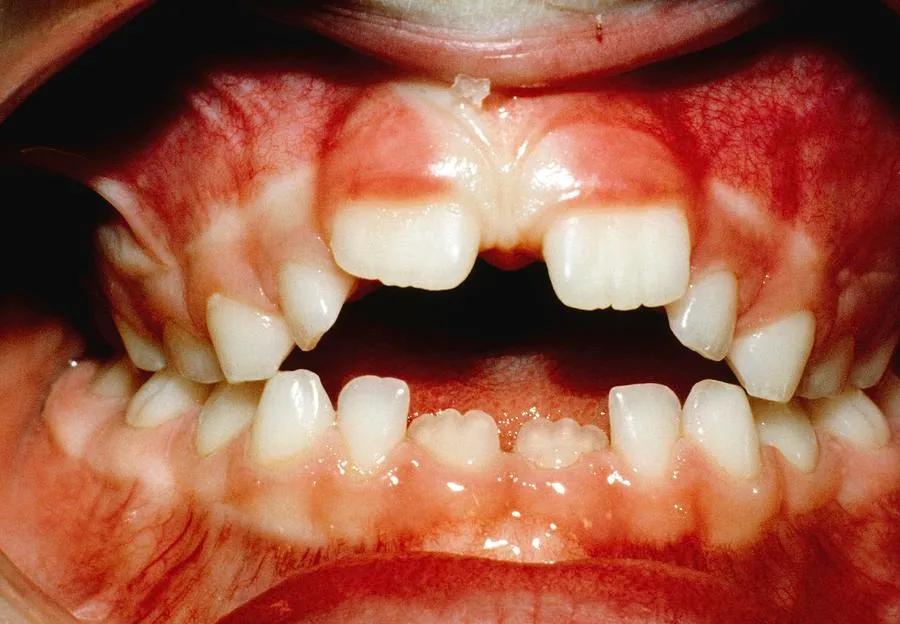

到了 4、5 岁,孩子开始长恒牙,频繁吃手会影响牙齿发育。而且,孩子也可能受到同伴的嘲笑。在开始帮孩子之前,同样应该排除会延长吃手习惯的因素,比如严重的情绪和压力问题。而且,要和孩子好好聊一聊吃手的负面影响,在他同意的情况下,一起来制定解决方案。

2、给孩子看吃手影响牙齿发育的图片。让孩子直观看到频繁吃手的坏处。还可以带孩子去看牙医,牙科医生的说的话可能他更能听进去。